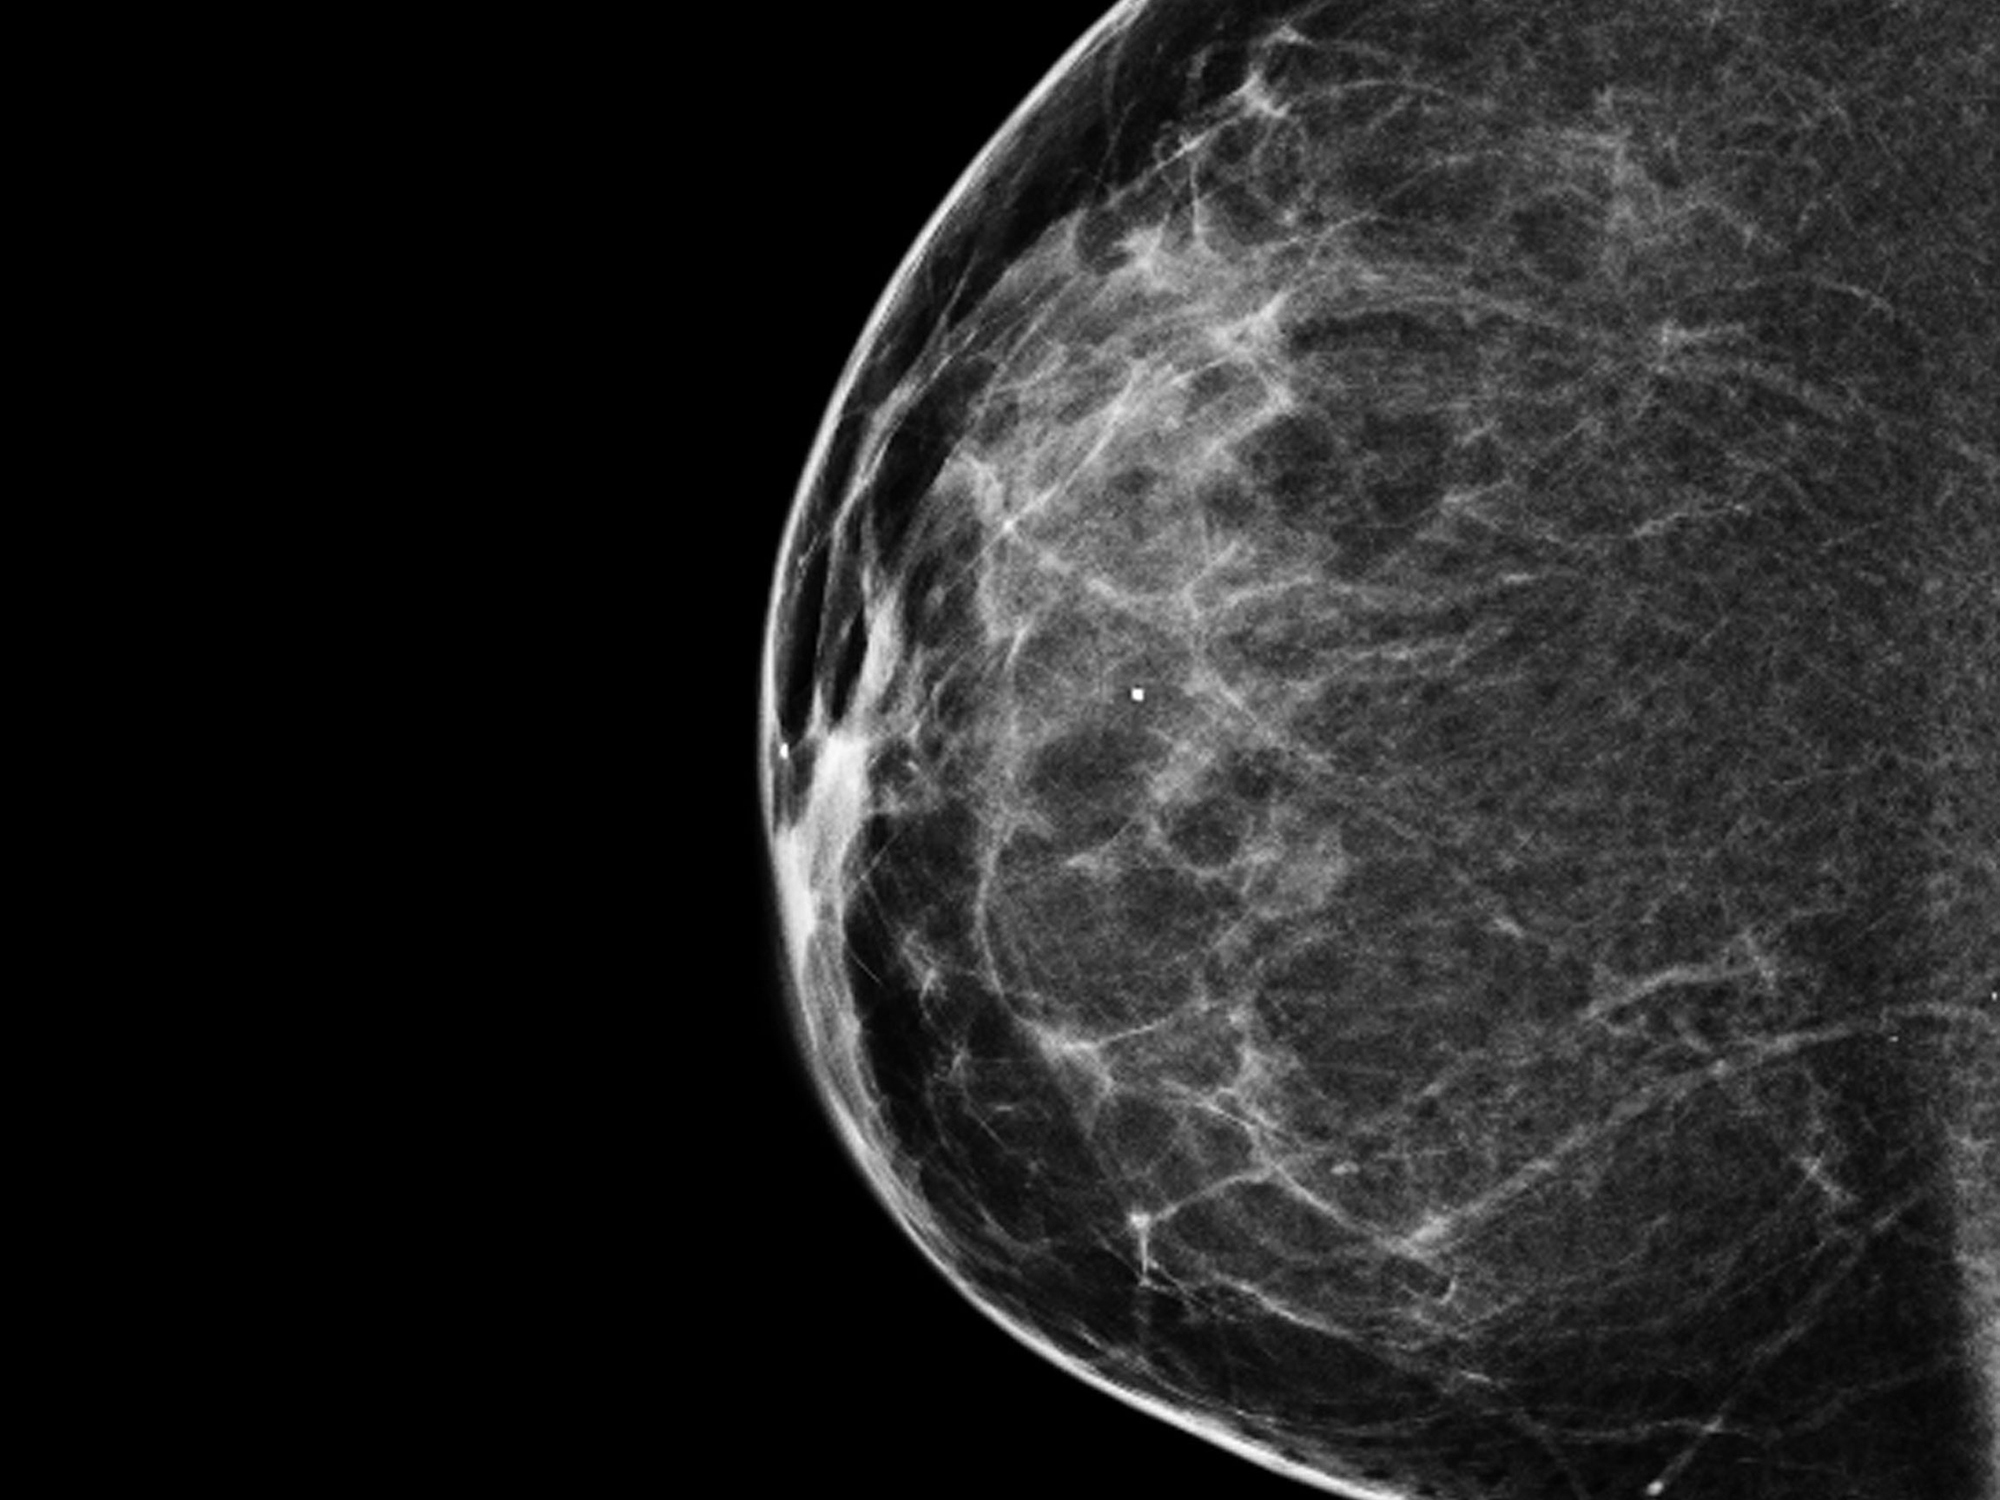

A 3-D mammogram reveals a normal breast. (National Cancer Institute)